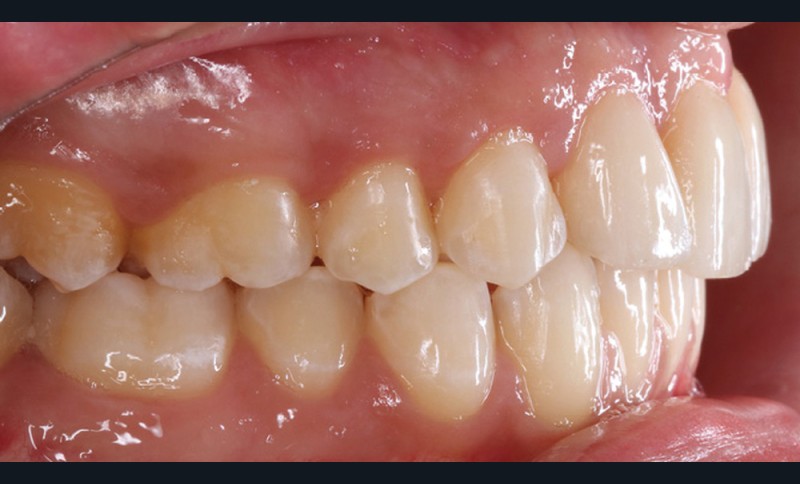

Le débaguage est réalisé au bout de 22 mois. Pour harmoniser la position des collets et redonner une hauteur coronaire acceptable aux nouvelles incisives centrales, une gingivectomie est effectuée, en accord avec le dentiste en charge des réalisations prothétiques. La croissance alvéolaire n’étant pas terminée, le rendu parodontal et esthétique évoluera. Ceci impose de différer la réalisation prothétique d’usage pour avoir un résultat stable dans le temps. Il est donc convenu de reprendre le traitement juste avant de réaliser les étapes prothétiques. Le traitement orthodontique comportant deux phases, les objectifs de finitions de la première phase sont abaissés pour réduire la durée globale de traitement.

Plusieurs difficultés ont été rencontrées durant le traitement. L’impact psychologique des extractions d’incisives centrales a été lourd pour le patient, dont la promesse d’un sourire harmonisé a permis de surmonter cette épreuve. Ensuite, la gestion de la transposition était délicate. Il a fallu également accepter un rendu esthétique perfectible jusqu’à la fin de la croissance. La gestion de la dysharmonie dento-parodontale au niveau des incisives latérales et des canines était essentielle ; une correction parodontale et orthodontique, en jouant sur les informations de deuxième et troisième ordres, a permis une transition esthétique optimisée. L’outil de prévisualisation Digital Smile Design s’est en ce sens avéré très utile pour définir les impératifs propres à la prothèse (fig. 4a,b). Des frais pour la parodontie et la prothèse se sont enfin ajoutés aux dépenses orthodontiques (deux phases de traitement). Le rendu esthétique est satisfaisant en fin de traitement, avec une harmonisation du sourire et du profil (fig. 5 et 6). Les extractions n’ont pas appauvri le sourire. La qualité des réalisations prothétiques, l’environnement parodontal remanié et l’occlusion de fin de traitement font espérer un bon devenir dans le temps.